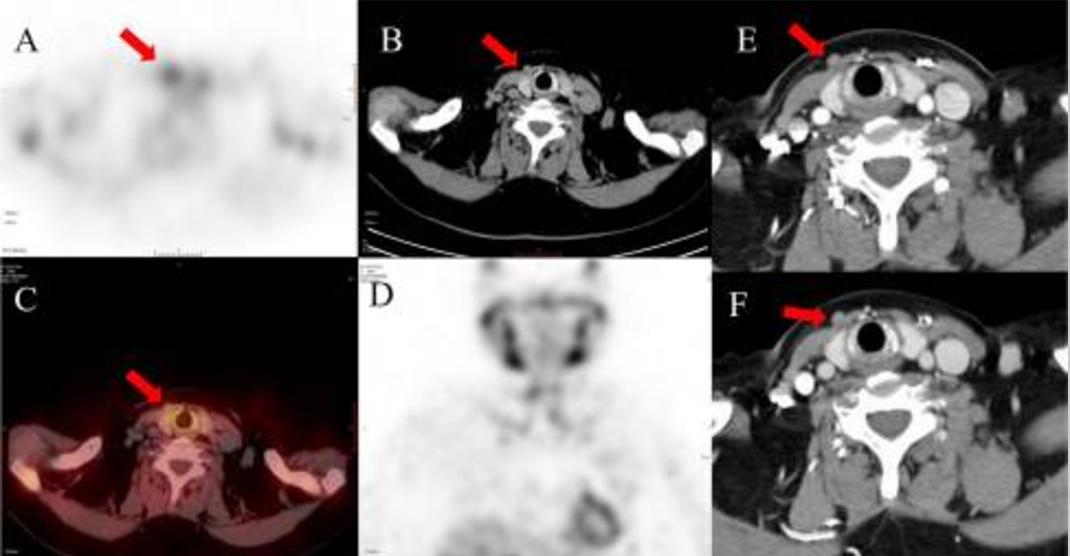

入院时,PTH、血清钙和磷酸盐分别为3356 pg/mL、3.22 mmol/L和1.39 mmol/L。99mTc-MIBI SPECT/CT显示左侧甲状腺下极积聚,与增强CT和超声检查结果一致(图2)。右颈前部皮下有一个示踪剂积聚的结节,与CT结果一致(图3)。

图2 99mTc-MIBI SPECT/CT扫描显示聚焦示踪剂积聚,位于左甲状腺下方的低密度结节(红色箭头:a SPECT、B轴位图像、C冠状SPECT/CT融合图像、D冠状SPECT图像)。对比增强CT扫描显示位于左甲状腺下方的中度增强的甲状旁腺结节(红色箭头)的动脉期(D)和延迟期(E)轴未图像。甲状腺左下叶有一个边缘不规则、钙质成分的低回声结节的超声图像(G)